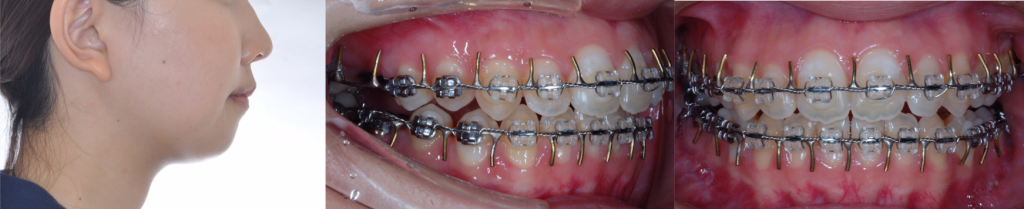

術後矯正治療終了時(ブラケット撤去) 23歳2カ月

骨固定用チタンプレート除去とオトガイ形成術同時施行、ホワイトニング施行(自費) 23歳6カ月